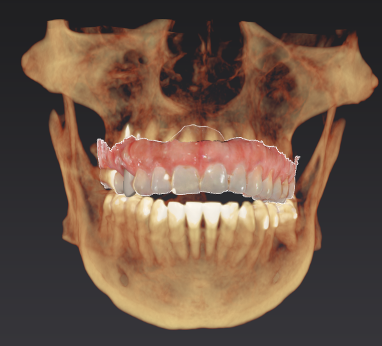

During your initial consultation at Arcadia Perio, Dr. Peterson will review your medical history, perform an oral exam, take digital X-rays, and likely consult your general dentist. Sometimes, a 3D scan is taken with our cone-beam computed tomography scanner to accurately visualize your unique anatomy and plan virtual implant treatment. The initial planning phase is as thorough as possible to optimize long-term success and determine your optimal solution.

Procedure & Same-Day Teeth

The 3D image we took during your consultation is used to create computer-aided guidance with our sophisticated X-Nav system. Visualizing the placement of your dental implants in 3D eliminates guesswork and potential complications. In the skilled hands of Dr. Peterson, proper planning combined with X-Guide Dynamic 3D Navigation during surgery elevates surgical excellence while increasing efficiency and safety. If you received full-mouth dental implants, our customized, streamlined protocol enables Dr. Peterson to fit you with temporary 3D-printed teeth within 24 hours of your surgical procedure.

Implant Treatment Planning

Clinical overview

3D planning

CBCT & planning

Planning detail

Additional planning view